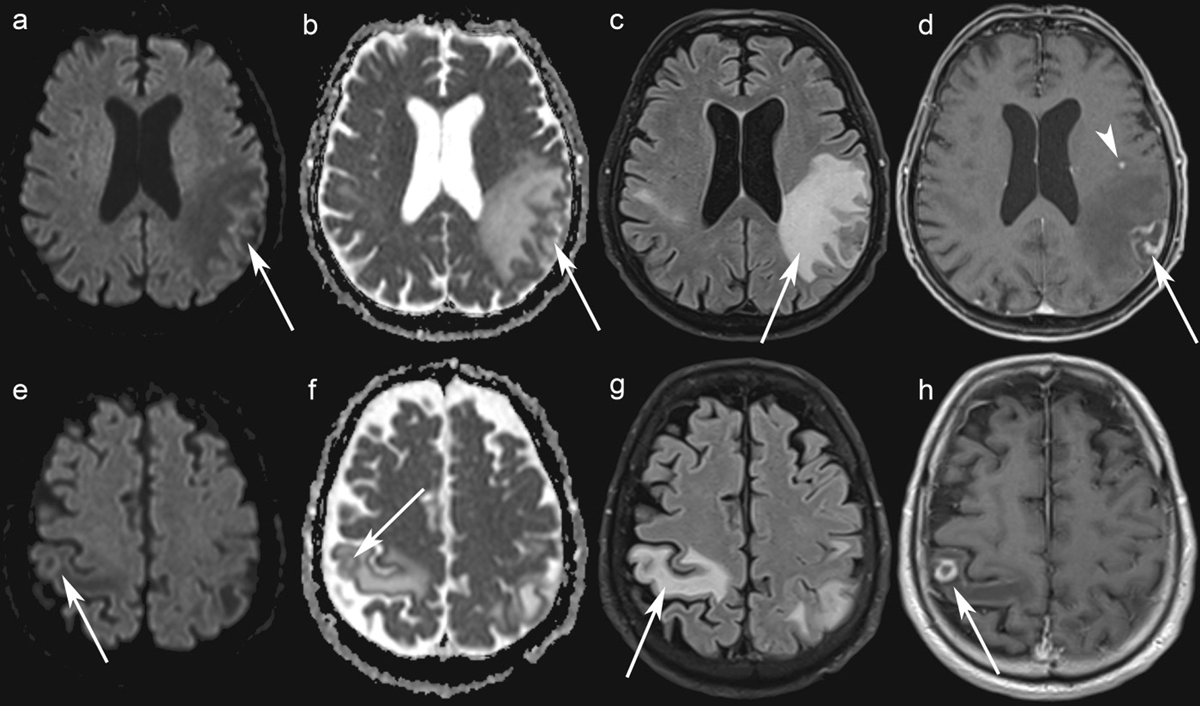

Figure 1

Brain MRI. Axial Diffusion-Weighted Imaging (b = 1500 s/mm²) show no increased signal in the left and right parietal lobe lesions (a, e) while axial ADC maps show a greater signal than that of the unaffected white matter (b, f) (arrows). Axial FLAIR images show edema around the lesions (c, g). Axial contrast-enhanced T1-WI shows rim-enhancing lesions in the left and the right parietal lobes (arrows) (d, h), and one punctate lesion in the left frontal lobe (arrowhead) (h).